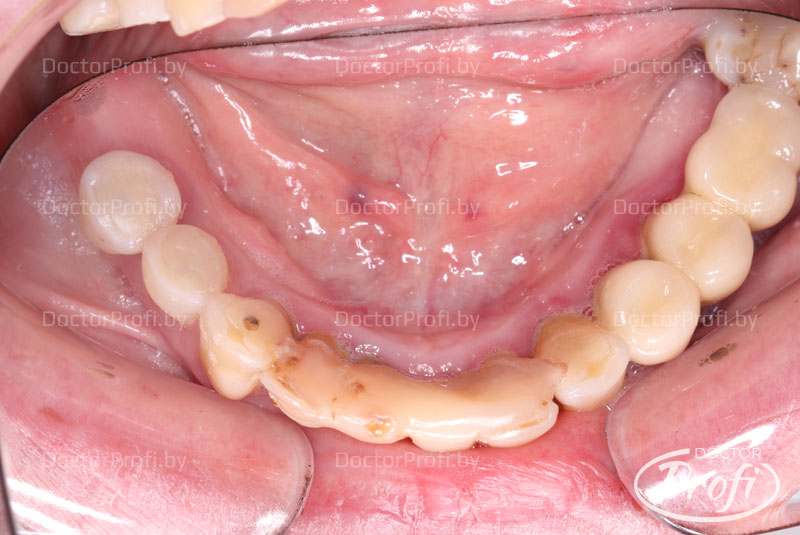

Хронический маргинальный периодонтит зубов верхней и нижней челюсти, резорбция костной ткани на 2\3 длины корней зубов, подвижность всех зубов 1-2 степени, хронический апикальный периодонтит, частичная вторичная адентия.

- Удалены все зубы на верхней и нижней челюсти.

- Удалены все воспалительные очаги.

- Одномоментно установлено 6 имплантов MegaGen AnyRidge на верхней челюсти и 6 имплантов MegaGen AnyOne на нижней челюсти.

- Сразу после операции сняты оттиски.

- На 7ые сутки фиксированы несъемные конструкции.